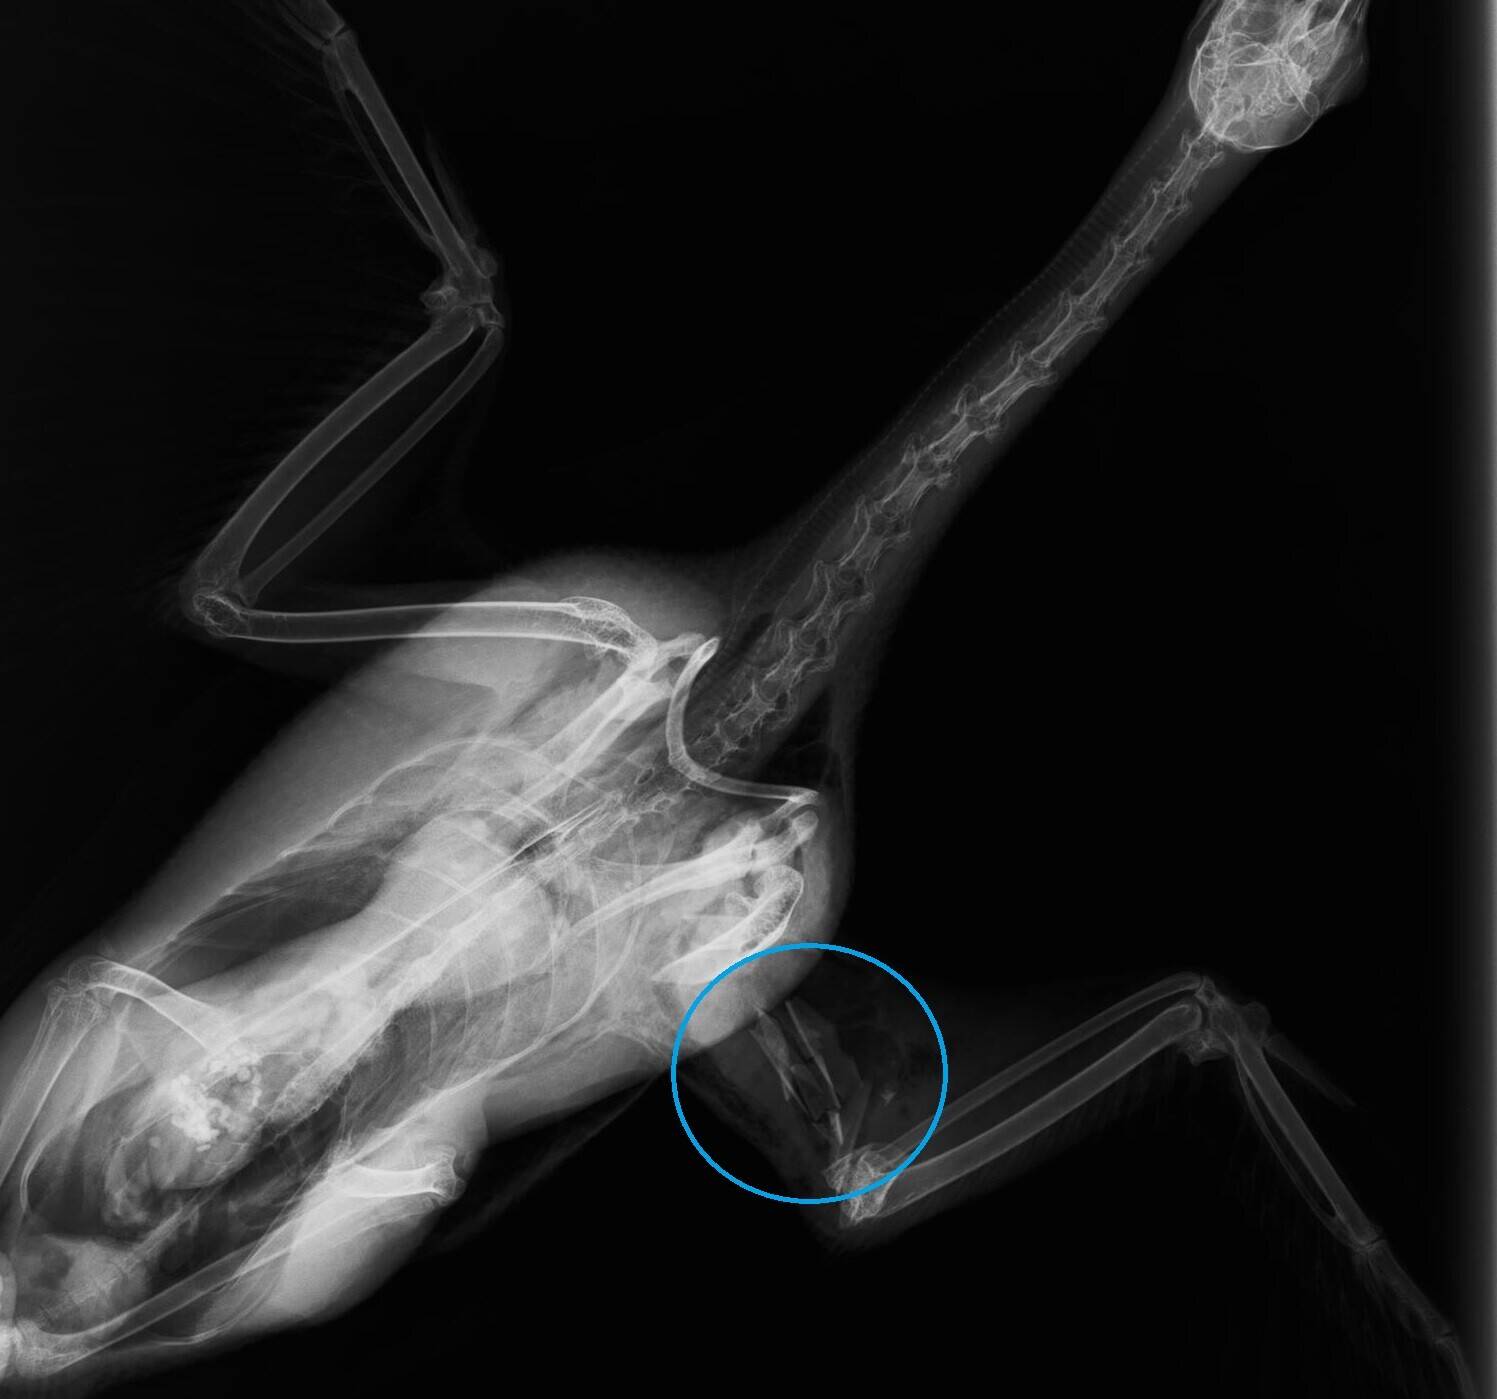

こちらの青丸は赤丸と同じ部位の骨折ですが、粉々になっているので粉砕骨折と言います。